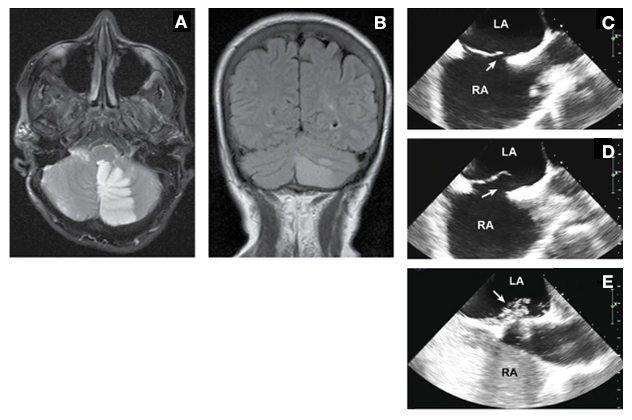

Large patent foramen ovale with an atrial septal aneurism requiring percutaneous closure

A 63-year-old woman with a remote history of migraine awakened with a headache with visual aura, as well as nausea, vomiting and incoordination. She was a former smoker but had no history of hypertension or estrogen replacement and no family history of stroke. A and B. MRI demonstrated a left cerebellar infarct. C and D. Transesophageal echocardiography demonstrated a large patent foramen ovale (arrow) with an atrial septal aneurysm. E. Contrast injection demonstrated generous flow across the patent foramen ovale (arrow) with Valsalva maneuver. Percutaneous closure was performed.